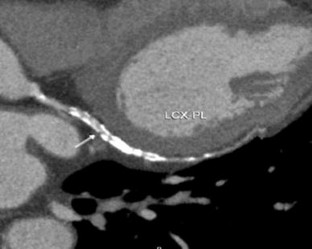

Fig. 2